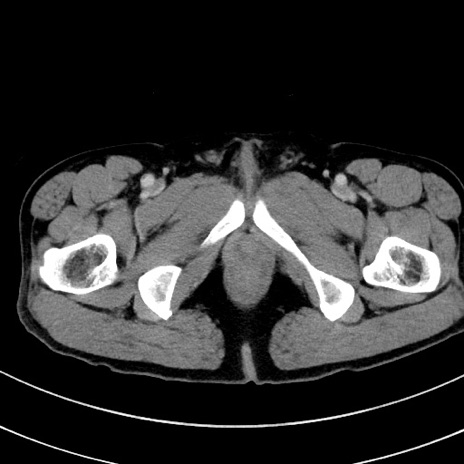

症例8(横断像)

【症例】 60歳代男性

【主訴】 黒色吐物

【現病歴】 4日前から嘔気自覚、2日前の朝食後にも嘔気あり、自分で手で嘔吐反射起こし嘔吐したところ血が混ざっていたため受診。

【既往歴】 5年前汎発性腹膜炎を伴う急性虫垂炎で手術、高血圧、前立腺肥大症、高脂血症

【身体所見】 腹部正中に手術癩痕あり 腹部平坦・軟圧痛なし膨満感あり

【データ】WBC 8400、CRP 4.54